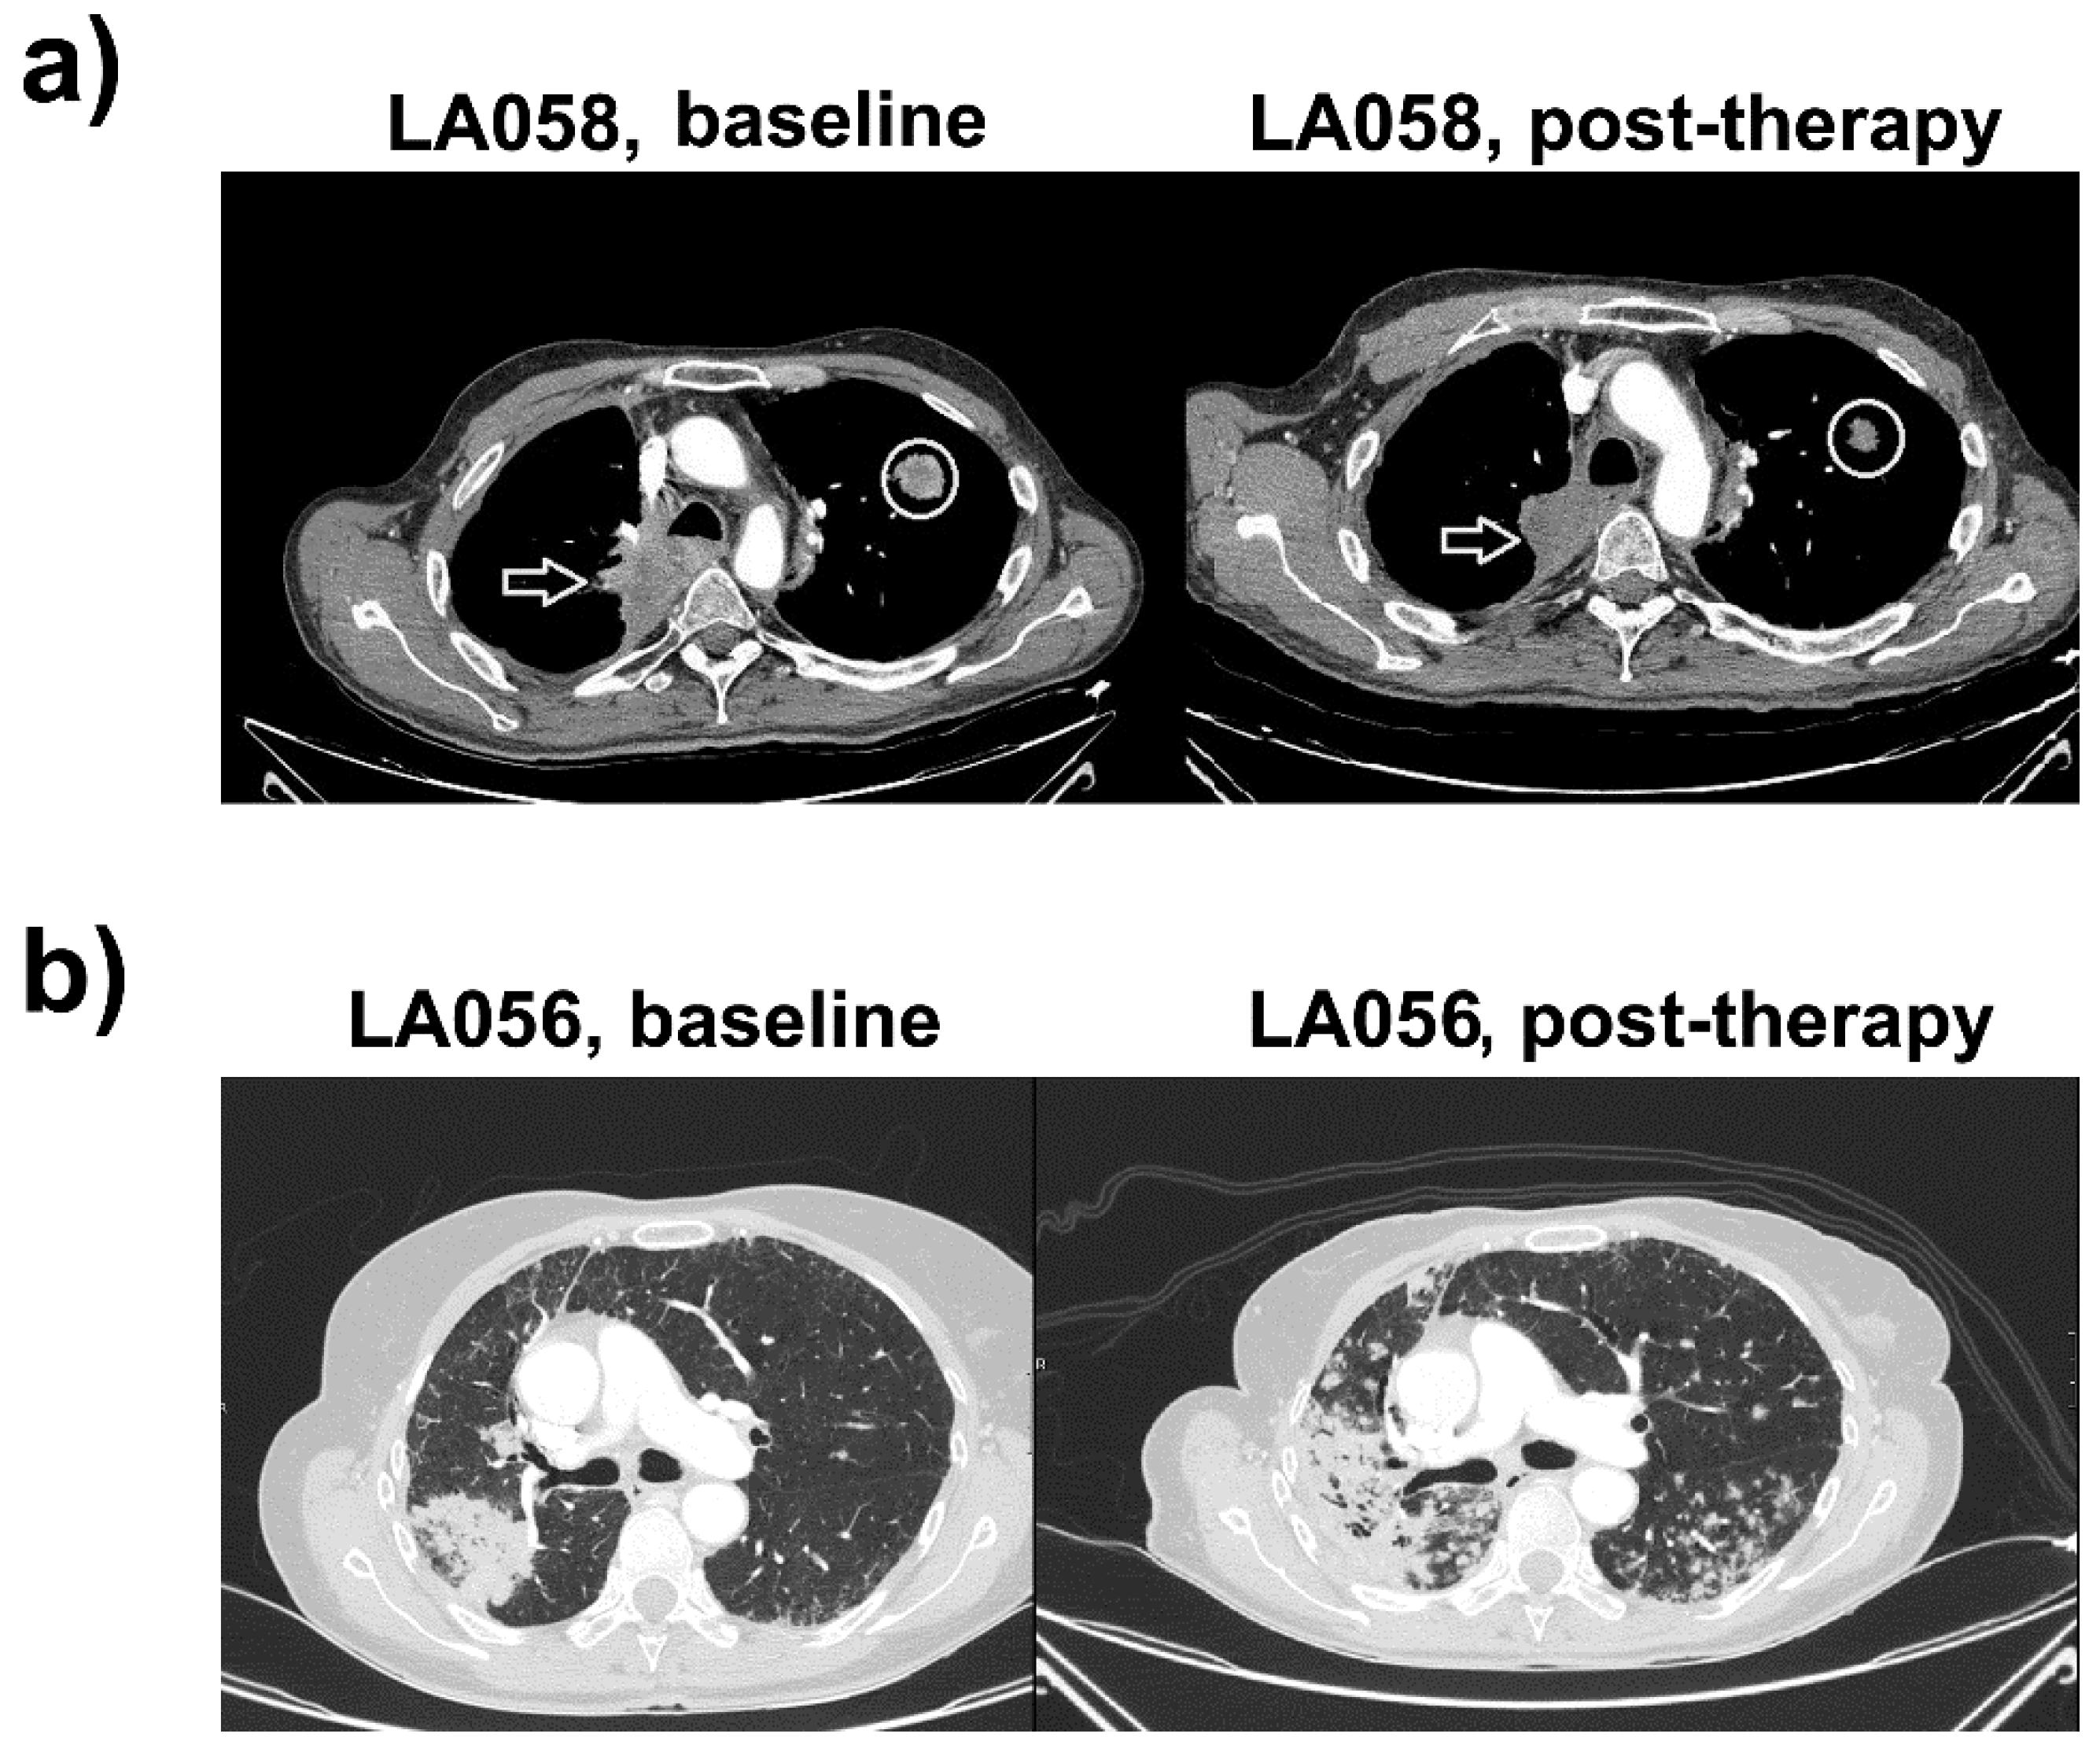

In April 2018, he presented progressive dyspnea and asthenia, with progression of the paravertebral mass and the ULL node (Figure 1a). PD-L1 expression in a tumor sample obtained by bronchoscopy was negative, and the status of ROS1 and ALK rearrangements and EGFR mutation were non-informative. Treatment with 1200 mg q21d atezolizumab (anti-PD-L1) was started, without significant side-effects and evident clinical improvement. The right paravertebral mass and the ULL node showed shrinkage after four cycles of therapy, and absence of new lesions, compatible with a partial response (Figure 1a). He is currently under treatment with adequate tolerance to treatment.

Figure 1.

Clinical responses for tumor PD-L1-negative patients LA058 and LA056 treated with atezolizumab. (a) Left, CT images of LA058 before the start of immunotherapy. Right, CT images of LA058 after atezolizumab, demonstrating objective clinical responses, with evident tumor shrinkage. Arrows indicate a paravertebral upper right lobe mass with mediastinal invasion and posterolateral wall of the trachea. The circle indicates a contralateral metastatic node in the upper left lobe. Both lesions show a marked morphological decrease compatible with a partial response. (b) Left, CT evaluation of the LA056 patient. A tumoral relapse in the site of previous surgical intervention is evident. Right, CT following atezolizumab treatment. Tumor progression with bilateral pulmonary nodes and increase of the lower right lobe (LRL) mass, consistent with fast progressive disease.

Patient 2 (LA056) is a 64-year-old woman with a smoking history of 40 cigarette packages per year and hypercholesterolemia, with long-lasting bronchopneumonia and a suspicious mass in the Lower Right Lobe (LLR). PET-CT scan uncovered a 7-cm-wide lesion in the LLR with high metabolic activity and another lesion in the Middle Right Lobe (Figure 1b). Results from fine-needle aspiration suggested an adenocarcinoma. Bilobectomy of the lower right lobe and the middle lobe was performed together with hilar-mediastinal lymphadenectomy. The patient was diagnosed with pT4N0M0 (stage IIIA) lung adenocarcinoma with ipsilateral nodes and lack of nodal involvement. Subsequent study of molecular markers in cancer cells (ALK, ROS1, EFGR mutations) were negative. PD-L1 expression in the tumor was null.

The patient underwent four cycles of adjuvant chemotherapy with intravenous cisplatin (80 mg/m2) on day one, plus vinorelbine (25 mg/m2) on days one and eight q21d, presenting grade two diarrhea. The patient presented progression with bilateral pulmonary nodes and tumor relapse at the previous surgical site. Palliative chemotherapy with pemetrexed (500 mg/m2 q21d) was initiated, achieving stabilization. After 10 cycles of treatment, CT scans showed an increase in the number and size of the pulmonary nodes (Figure 1b).

Treatment with atezolizumab was initiated. The patient presented fever, cough, and progressive dyspnea after six cycles. Increases in the number and mass of contralateral pulmonary nodes without implication of bacterial or fungal infections was observed, consistent with progressive disease (Figure 1b).